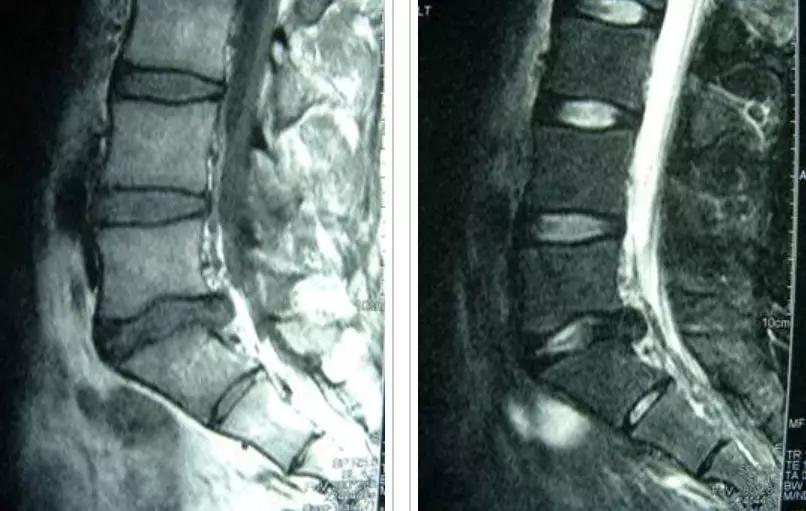

图:17岁男孩,因“腰痛伴右下肢放射痛6个月”就诊

MRI提示腰5-骶1椎间盘突出

青少年与成人LDH都可出现腰腿痛,但 青少年LDH症状通常较轻,神经功能损害(如感觉障碍、肌力下降等)较少见 ,而直腿抬高试验阳性率则可高达90%,而且常呈强阳性,多限于<30°范围。

与成人LDH相比, 青少年LDH患者出现腰椎畸形的比例较高,常见腰部僵硬、脊柱侧凸或旋转,常凸向患侧 ,这种畸形通常是由于疼痛而产生的代偿性脊柱侧凸。